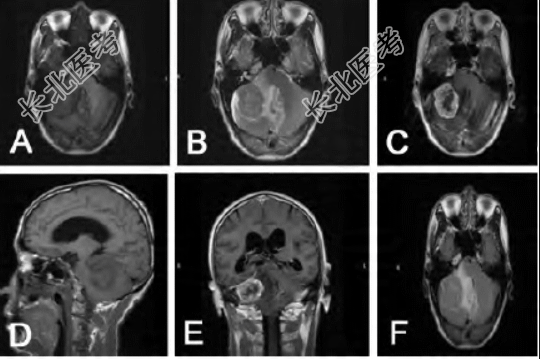

患者,男,68岁,因头晕头痛伴行走不稳1个月入院。既往2年前曾行胰腺肿瘤切除术,术后病理检查示低分化胰头腺癌,术后病情稳定,按期入院接受随访,同时给予“卡培他滨+吉西他滨”化疗,未见明显异常。入院时体格检查:神志清楚,GCS评分15分;双侧瞳孔等大、等圆,直径约2.5 mm,对光反射灵敏;颈软,无抵抗;听力正常;四肢肌力5级,肌张力正常;指鼻试验阳性,轮替试验阳性,跟膝胫试验阳性,双下肢病理征未引出。外院颅脑CT示右侧桥小脑角区边界清晰类圆形肿块,等稍高密度,周围可见不规则水肿带环绕。入院后颅脑MRI平扫及增强显示右侧桥小脑角区团片状病灶,信号欠均匀,呈等T1、稍长T2混杂信号;T2 Flair呈混杂等高信号,内可见片状地信号灶,病灶可见分叶,边界清晰,呈宽底与邻近脑膜关系密切;增强后可见周围脑膜明显强化,最大层面约4.2 cm×3.6 cm×2.7 cm,可见明显脑膜尾征。术中见肿瘤组织呈灰色,无明显包膜,质地较脆,与天幕轻度粘连,基本切除病灶。术后病理检查考虑转移瘤。